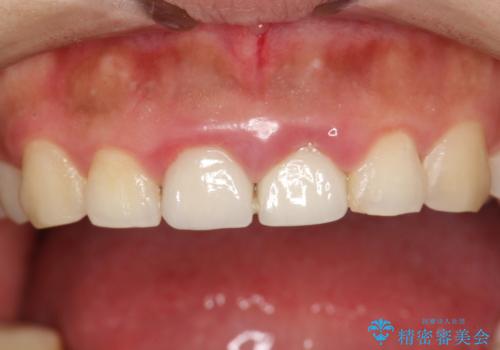

終了時

かなり久しぶりの歯科医院との事で、全体的に古くからの歯垢・歯石が多く付着していたため、自費クリーニング(PMTC)60分コース・歯周ポケット検査(保険適応)を行いました。

磨き残しが放置されると、そこで病原菌が繁殖し始めます。よって歯肉に炎症が生じ、歯周病の原因になることがあります。

定期的に、歯周病検査や専門的なクリーニングをすることで、早期発見につながります。